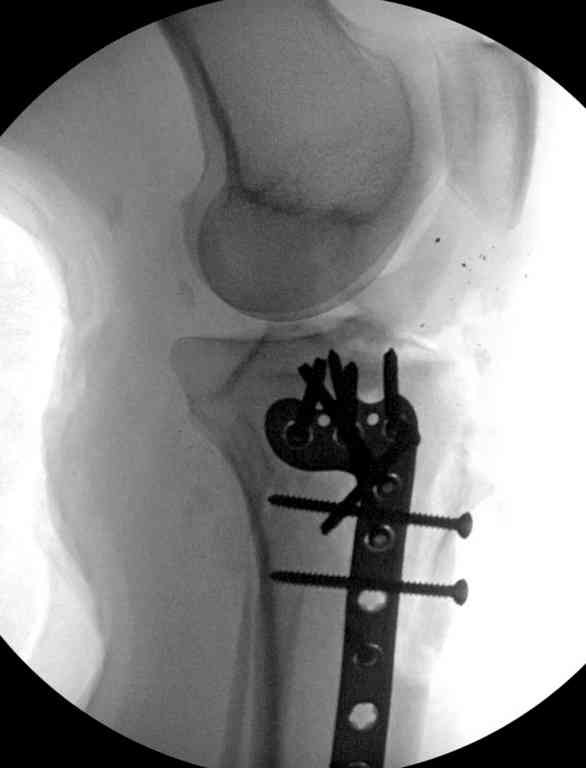

Здесь применение материала Plexur http://www.plexur.com для пластики при дефектах кости у больной с огнестрельной раной латерального тибиал плато с повреждением малоберцового нерва. Несмотря на интактный медиальный мышелок, для профилактики от вальгуса установлен АВФ и сделана ангиограмма.

После нескольких обработок и вакуумирования, поэтапно сделана фиксация тибиального бугра шурупами. И окончательную фиксацию закончили латеральной пластиной для тибиал плато и установкой пластического материала.

Для закрытия мягкотканых дефектов привлечена другая служба.